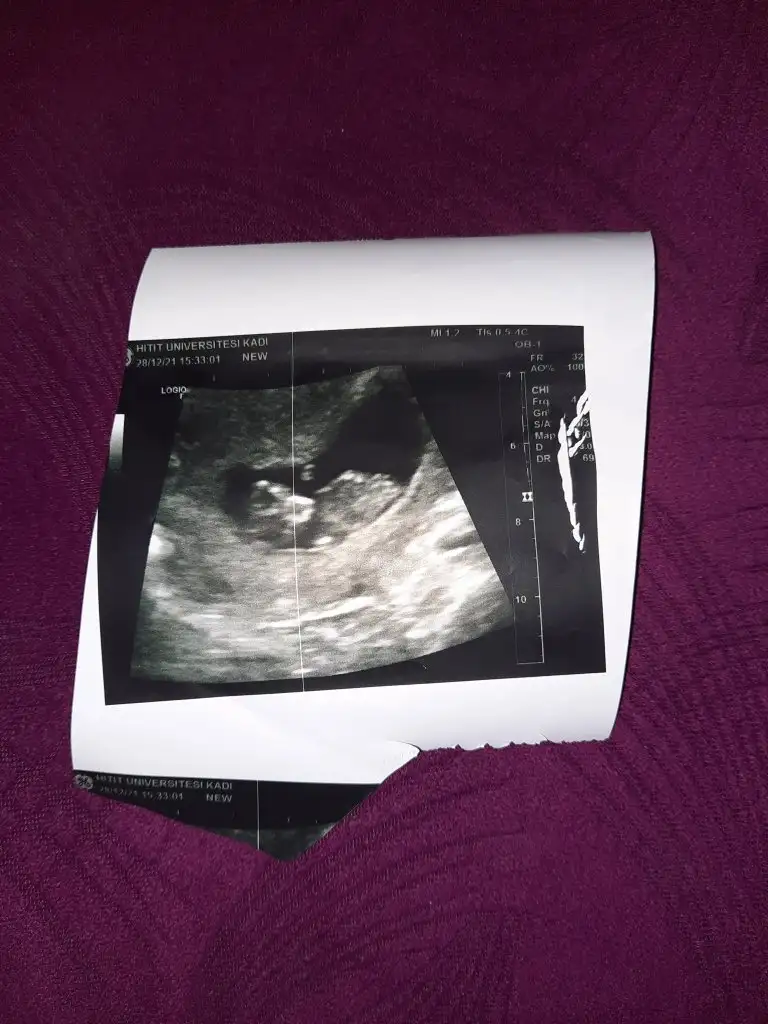

Kiz gibi sanki emin olamadımEki Görüntüle 2977845 İkra Meyra bizede bakabilir misin 12+4